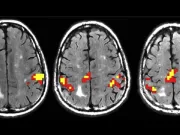

O parte surprinzătoare a creierului tău devine mai puternică pe măsură ce îmbătrânești

Contrar așteptărilor, nu toate părțile creierului degenerează odată cu vârsta. O nouă cercetare arată că, în timp ce unele regiuni se subțiază, anumite straturi...